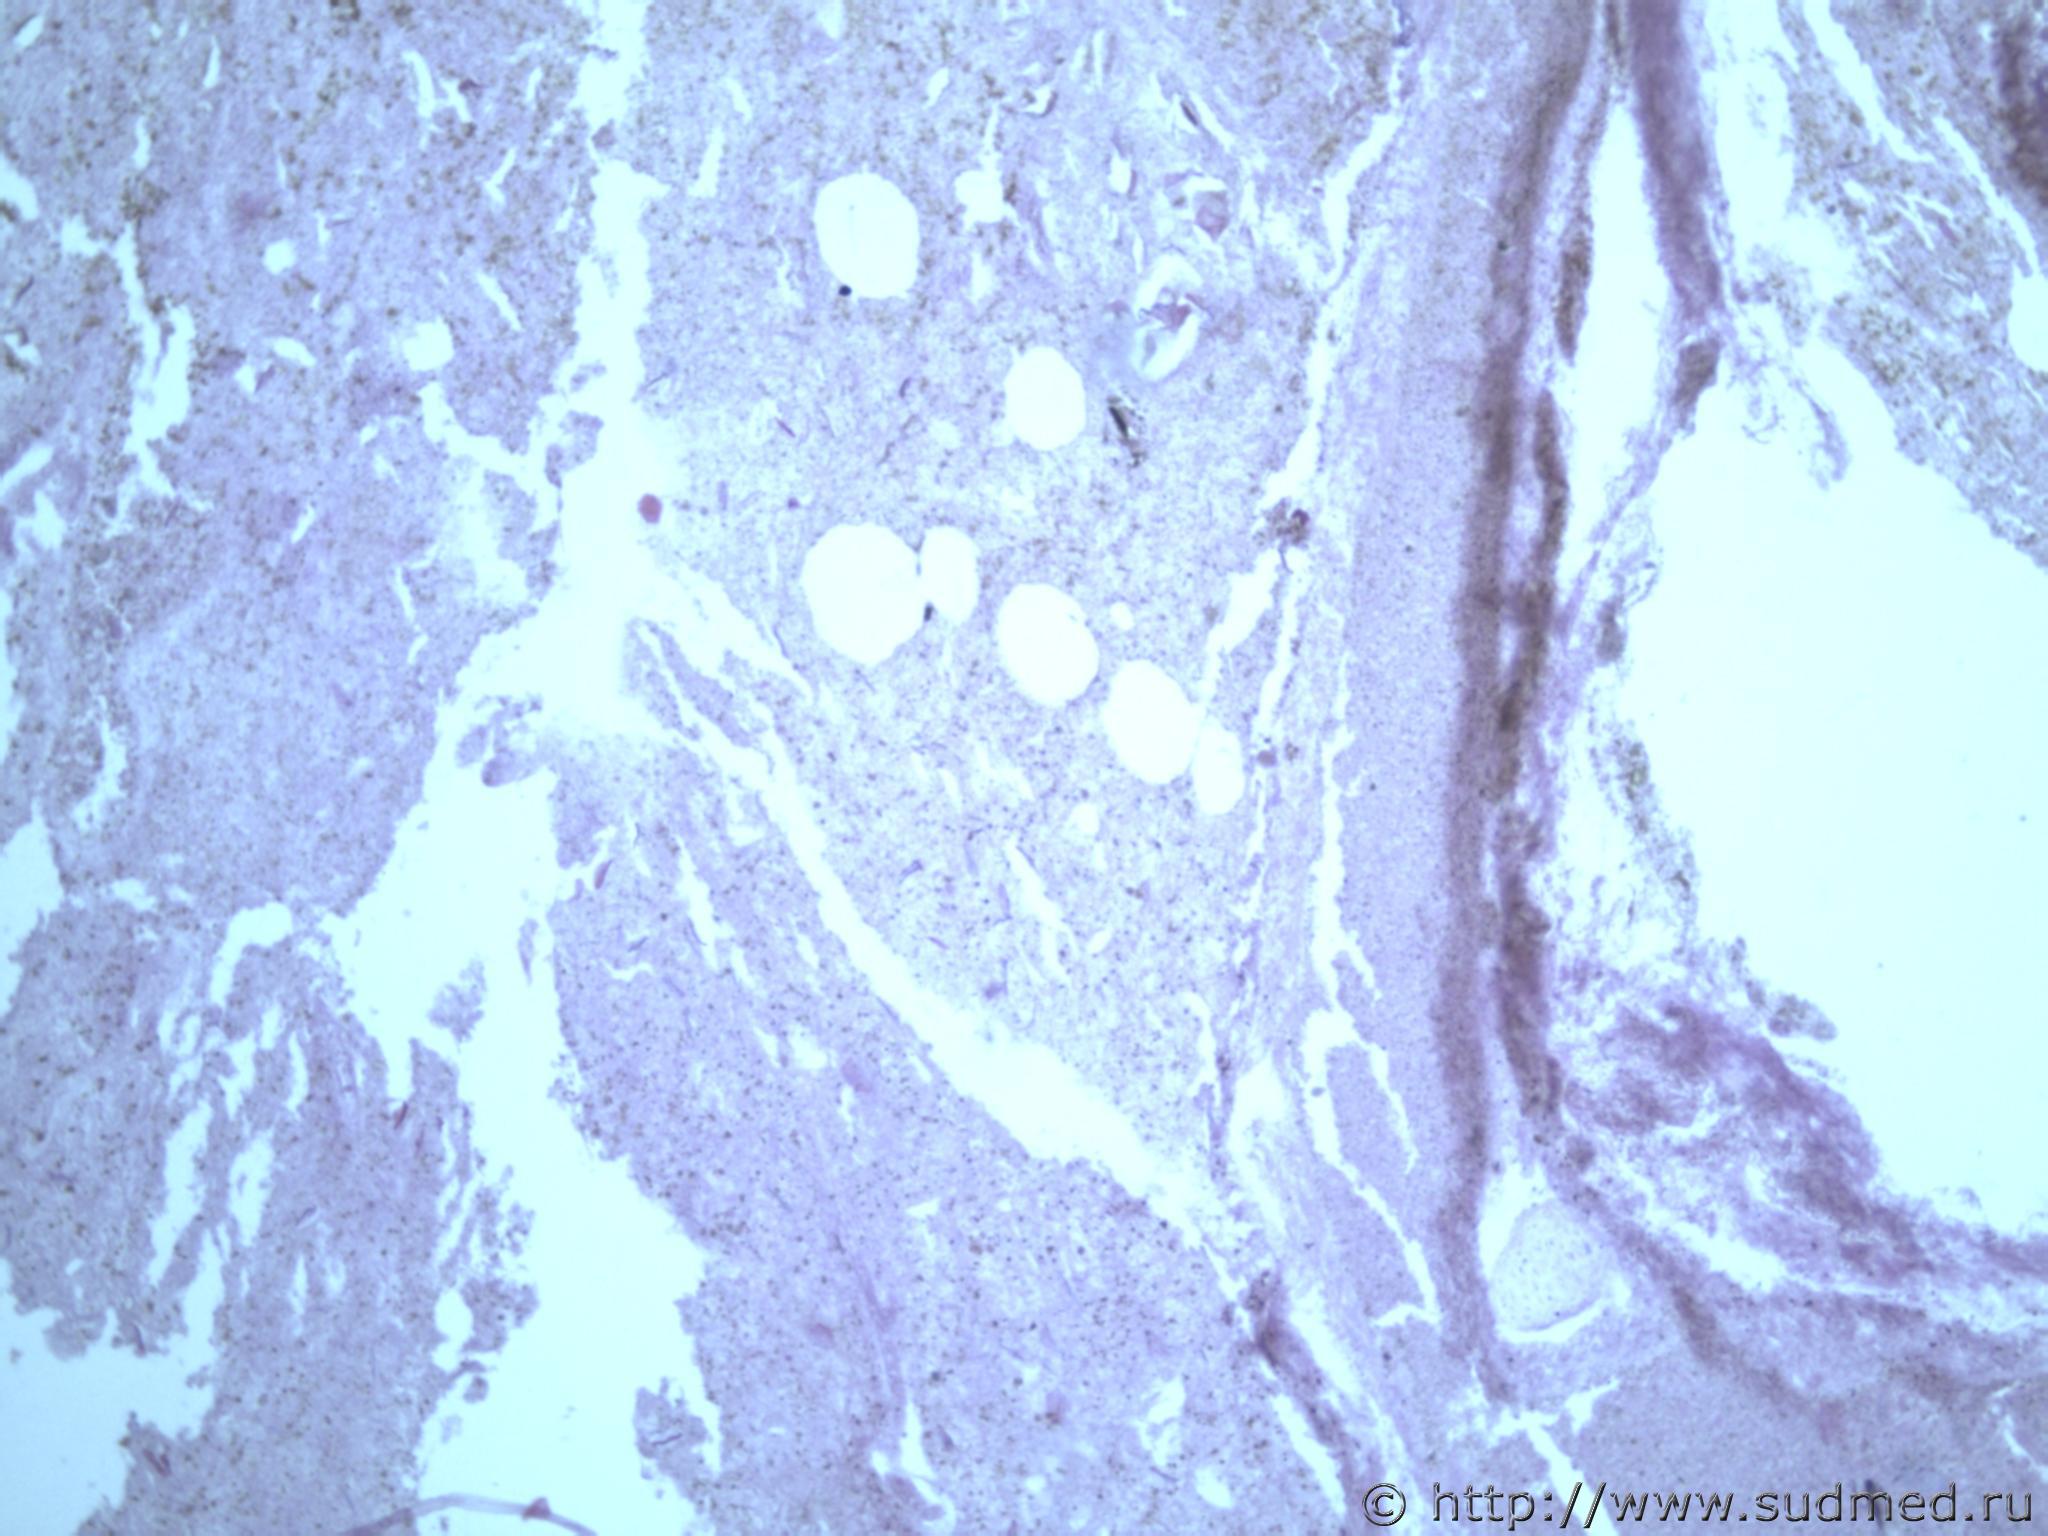

всем здравствуйте. хотела бы знать ваши мнения. провожу экспертизу. препараты как и труп новорожденного гнилые либо в аутолизе страшном. в легком картина такова, что ткань "плотная". просвет различимых альвеол в виде щелей и по всем полям зрения элементы околоплодных вод. одна артерия пуповины спазмирована. остальные сосуды непонятно : просвет их спавшийся но без признаков спазма. они как будто сплющены. да и сама пуповина в виде тонкого тяжа, видно из-за гнилостных изменений. под тмо спинного мозга признаки кровоизлияния, как и в коже с шеи. в коже головы с полнокровием отдельных сосудов. мать утверждает что ребенок после родов не сразу но все же шевелился и кричал. хотя перед этим он выпал у нее из матки на пол, ударившись головой. и со слов матери у него была пена изо рта и он хрипел.

Судебная медицина - Прикрепленное изображение Судебная медицина - Прикрепленное изображениеСудебная медицина - Прикрепленное изображениеСудебная медицина - Прикрепленное изображениеСудебная медицина - Прикрепленное изображение

Плохо,материал гнилой.

Остановился бы на дышавшем лёгком.

5 фото в сообщении №4 и 8 фото в сообщении №5 не наводит ли на мысль о дышавшем лёгком ?

Про остальные фото молчу,там или ничего не видно или же есть оптически пустые пузыри,что вероятнее всего,проявления гниения.